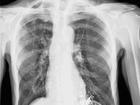

舌下神經是十二對腦神經的最后一對,其損傷在臨床上很常見,往往以復合在與延髓相關的病變和后組腦神經的臨床表現中,有時也以單一的損傷形式出現。下頜后間隙、頜下區、口腔或下頜骨水平支的火器傷、骨折和手術誤傷,可以發生舌下神經的單獨損傷。神經周圍的挫傷、出血、局麻浸潤引起的神經癱瘓,一般是暫時性的,或只遺留輕微殘跡。神經的粗暴挫傷或斷裂則表現為患側舌肌癱瘓,伸舌時舌尖向患側偏斜,以后萎縮。